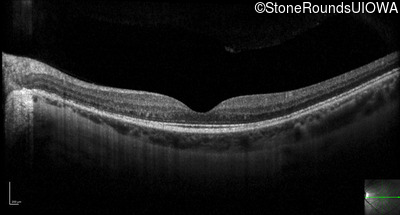

Optical Coherence Tomography - Left - 20/50

Exemplar / OCT Stack

OCT Stack